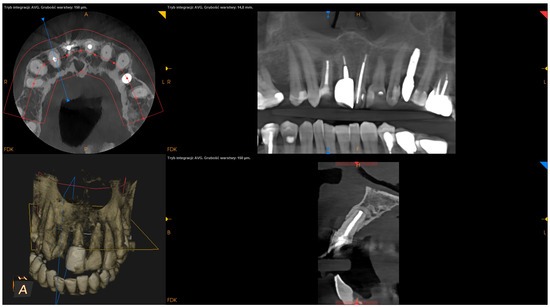

- The status of radiographic healing (rated in all sections, according to modified PENN 3D criteria [28]) was classified as complete healing (Figure 1), incomplete healing (Figure 2), uncertain healing (Figure 3), or unsatisfactory healing (Figure 4).

Figure 4. CBCT image (CS 8100 3D Carestream Dentalⓡ) example of unsatisfactory healing based on PENN 3D criteria. Non-English annotations present software technicalities (AVG integration mode and layer thickness).